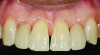

(1.) Pretreatment smile photograph of a patient with a maxillary left “peg” lateral incisor (tooth No. 10).

Figure 1

(2.) Posttreatment smile photograph after delivery of a no preparation leucite-reinforced ceramic veneer with a light-cure only resin cement.

Figure 2

(3.) Posttreatment retracted close-up view of the tooth No. 10 veneer.

Figure 3

For indirect restorations, such as inlays, onlays, veneers, and crowns, with reduced wall height and/or excessive wall taper, the use of a dentin bonding agent and resin cement is ideal. Both older and newer glass ceramics have a well-documented track record of success with this approach, regardless of the preparation type selected. Ideally, any enamel involved is etched with phosphoric acid and a dentin bonding agent is used. For glass ceramics that are less than 1.0-mm thick, a light-cure only resin cement might be preferred to minimize the risk for color shift over time (Figure 1 through Figure 3). Meanwhile, ceramic restorations that are greater than 1.0-mm thick are better delivered with a dual-cure resin cement to ensure adequate polymerization of the cement. In either case, photopolymerization of the dentin bonding agent prior to placement of the restoration with resin cement produces much higher bond strengths. Practitioners using dentin bonding agents with low film thicknesses (ie, 5 to 25 microns) should be able to predictably perform this step at the time of delivery. Practitioners who choose to use dentin bonding agents with higher film thicknesses must either co-polymerize the dentin bonding agent with the resin cement, which can lead to lower bond strengths, or utilize a technique such as immediate dentin sealing.